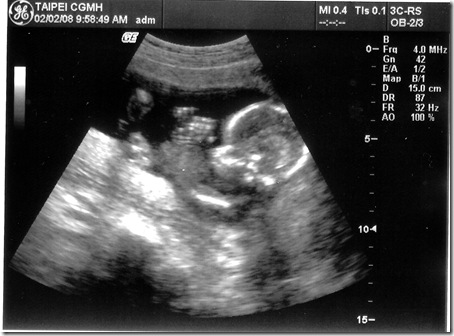

[產檢] 17週 寶寶頭大不是我的錯~~ ><

感覺有點擠~~

項  目 數 據 結 果 備 註

地點 02/02台北長庚 例行產檢

週數 17週

身長 15cm 體重約200g  ;  OK

心跳 150下/分鐘 OK

其他檢查 唐氏症抽血篩檢 預約高層次超音波

這星期主要還是看看超音波

量量寶寶的身長和估算體重有沒有在正常範圍

老婆邊照邊說寶寶頭很大..

沒想到醫生還跟著老婆瞎起鬨

說寶寶頭大像爸爸喔!!!   (明明寶寶頭的比例本來就比身體大得多...)   生氣...

這次照的超音波照也很清楚喔!!  真讚!!

寶寶還擺出鹹蛋超人的手交叉的動作..  五根手指己經看得清清楚楚了